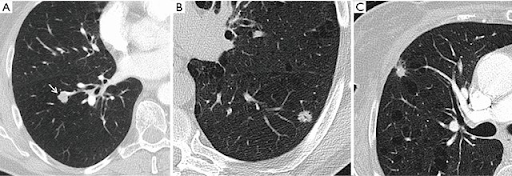

Humans can't detect race better than chance, but AI performs absurdly well on the task. As you can see here, AUC scores are in the high 90s, and are maintained on external validation on completely distinct datasets and across multiple different imaging tasks.

We performed many experiments to work out how it does this, but couldn't pin it down.

This is the most ridiculous figure I have ever seen. AI can detect race from images filtered so heavily they are just blank grey squares! (see the bottom right of the figure)